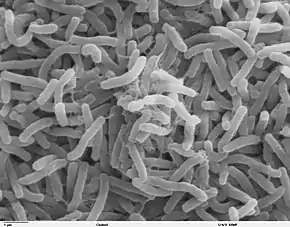

| Causes | Vibrio cholerae spread by fecal-oral route[2][4] |

Cholera is caused by a number of types of Vibrio cholerae, with some types producing more severe disease than others.[2] It is spread mostly by unsafe water and unsafe food that has been contaminated with human feces containing the bacteria.[2] Undercooked shellfish is a common source.[9] Humans are the only known host for the bacteria.[2] Risk factors for the disease include poor sanitation, insufficient clean drinking water, and poverty.[2] Cholera can be diagnosed by a stool test,[2] or a rapid dipstick test, although the dipstick test is less accurate.[10]

V. cholerae also exists outside the human body in natural water sources, either by itself or through interacting with phytoplankton, zooplankton, or biotic and abiotic detritus.[26] Drinking such water can also result in the disease, even without prior contamination through fecal matter. Selective pressures exist however in the aquatic environment that may reduce the virulence of V. cholerae.[26] Specifically, animal models indicate that the transcriptional profile of the pathogen changes as it prepares to enter an aquatic environment.[26] This transcriptional change results in a loss of ability of V. cholerae to be cultured on standard media, a phenotype referred to as 'viable but non-culturable' (VBNC) or more conservatively 'active but non-culturable' (ABNC).[26] One study indicates that the culturability of V. cholerae drops 90% within 24 hours of entering the water, and furthermore that this loss in culturability is associated with a loss in virulence.[26][27]

When consumed, most bacteria do not survive the acidic conditions of the human stomach.[31] The few surviving bacteria conserve their energy and stored nutrients during the passage through the stomach by shutting down protein production. When the surviving bacteria exit the stomach and reach the small intestine, they must propel themselves through the thick mucus that lines the small intestine to reach the intestinal walls where they can attach and thrive.[31]

Once the cholera bacteria reach the intestinal wall, they no longer need the flagella to move. The bacteria stop producing the protein flagellin to conserve energy and nutrients by changing the mix of proteins that they express in response to the changed chemical surroundings. On reaching the intestinal wall, V. cholerae start producing the toxic proteins that give the infected person a watery diarrhea. This carries the multiplying new generations of V. cholerae bacteria out into the drinking water of the next host if proper sanitation measures are not in place.[32]